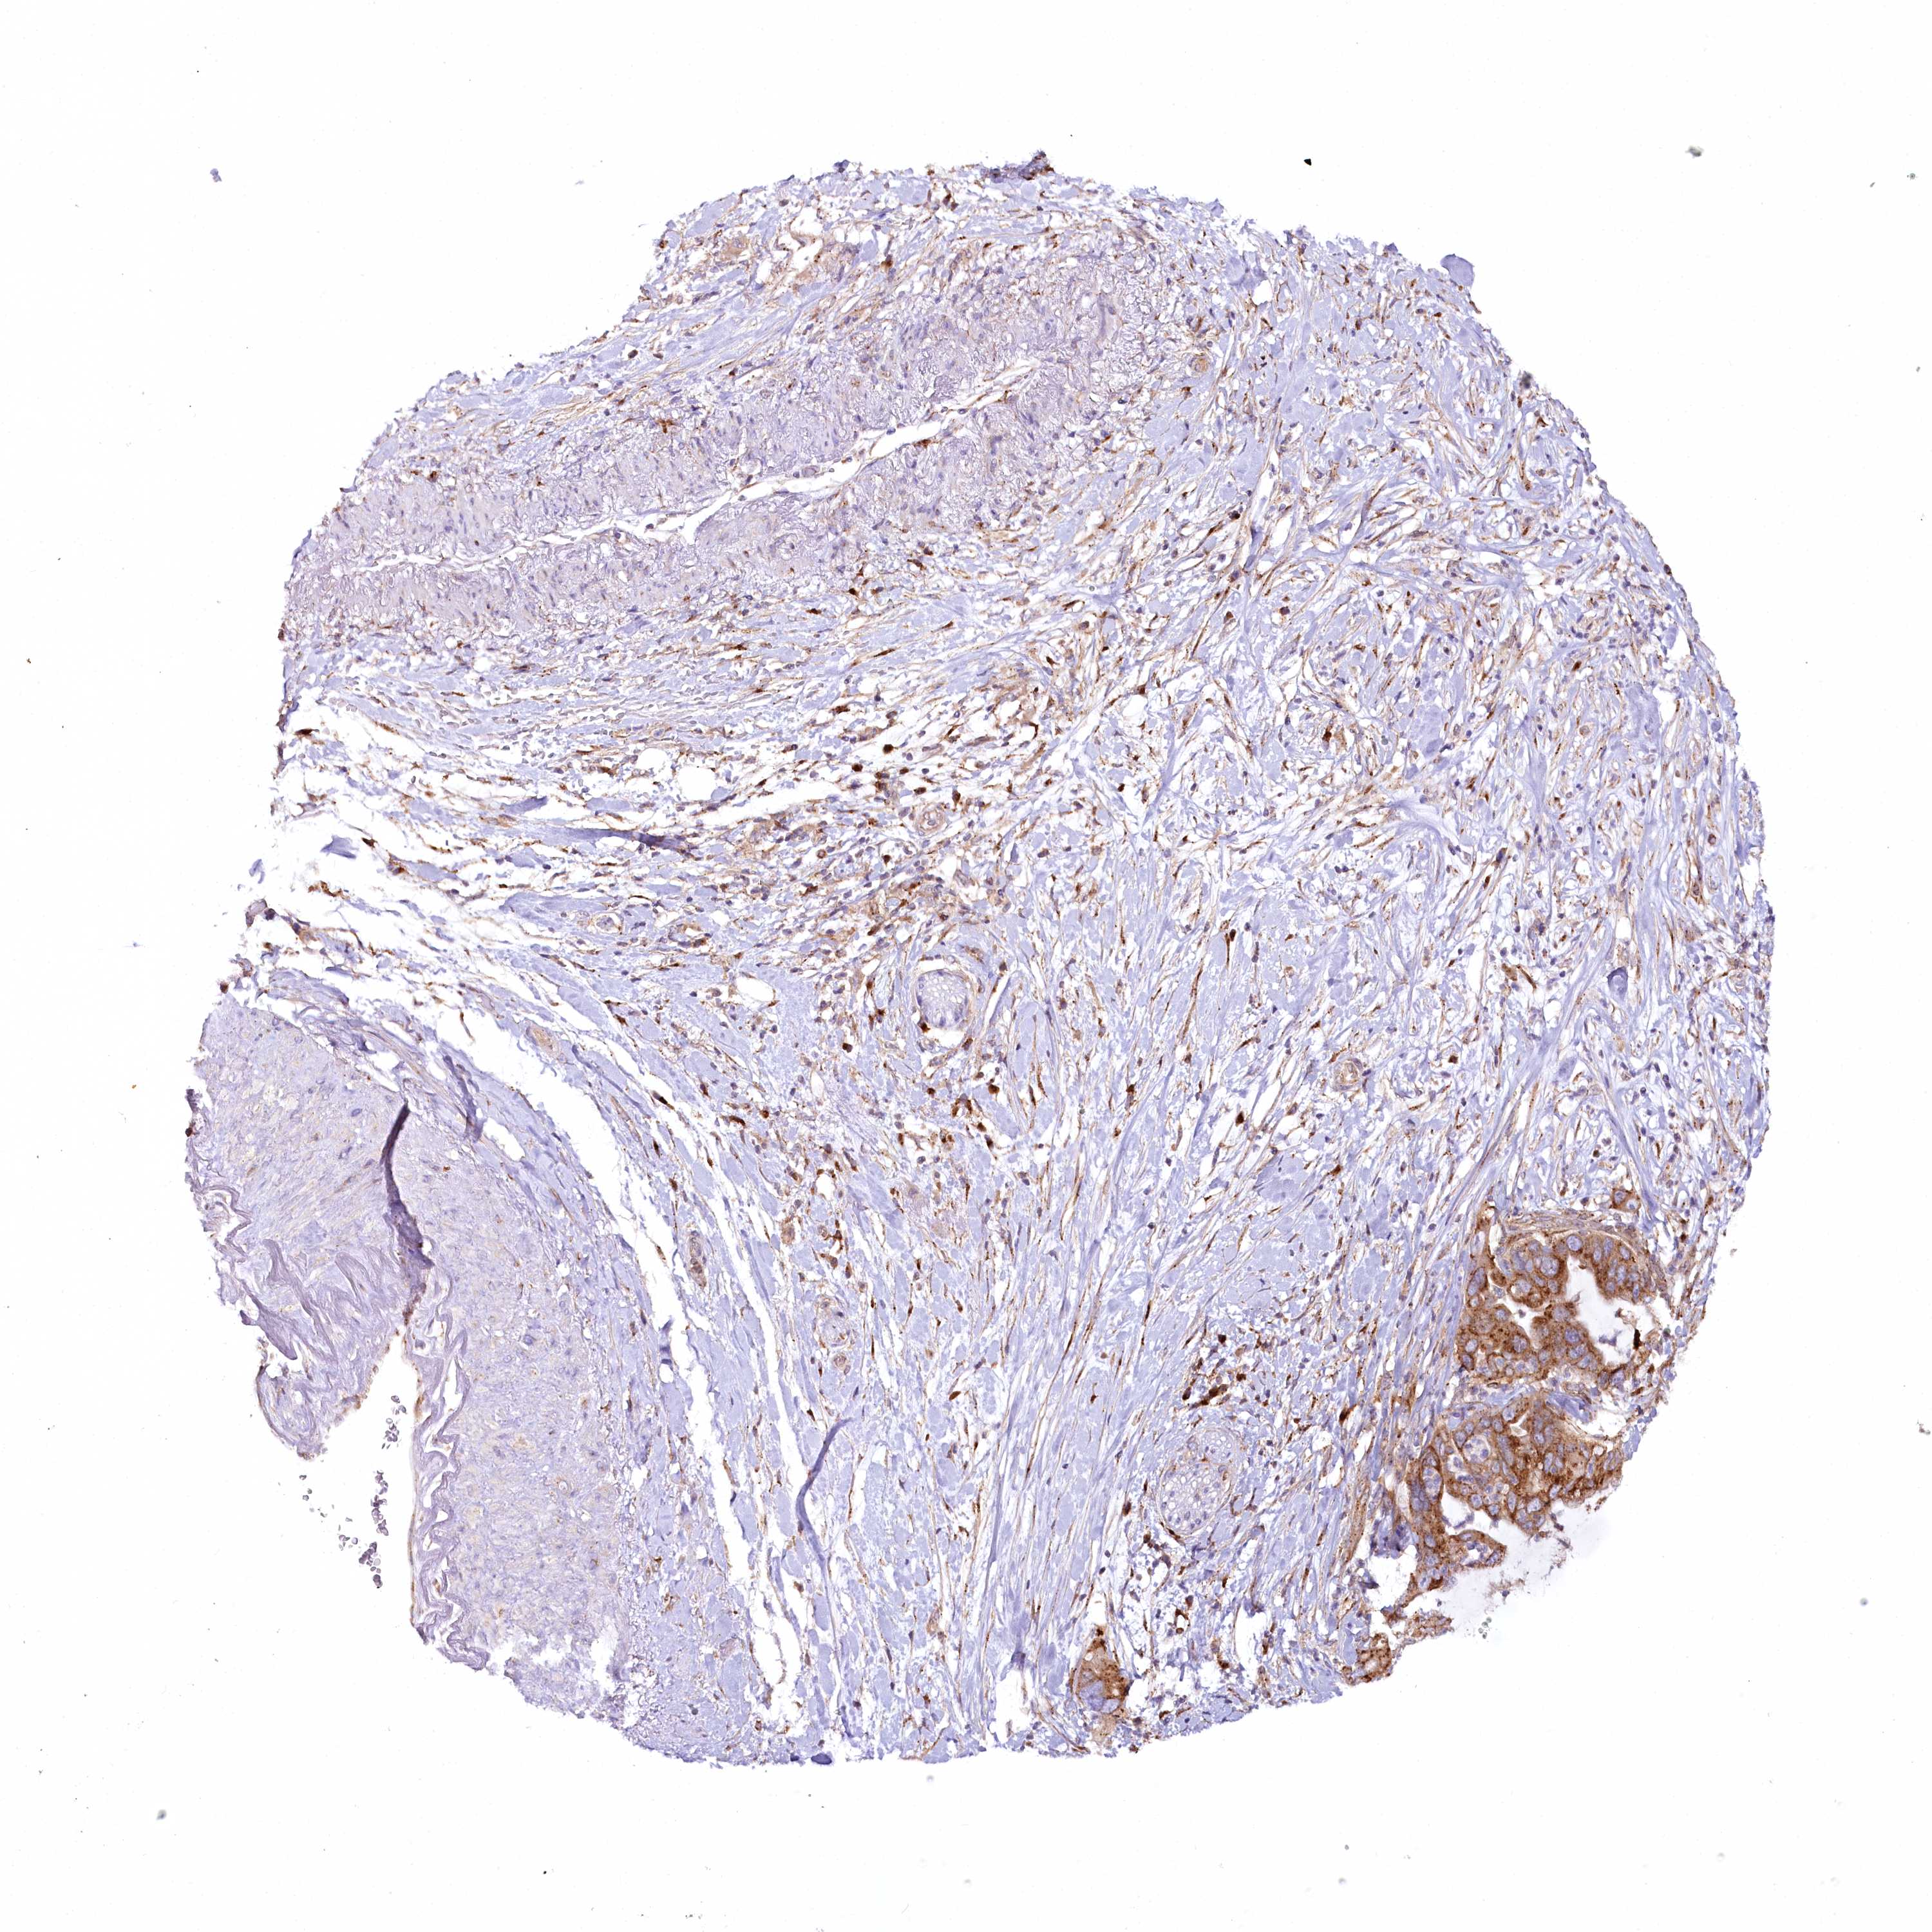

PANCREATIC CANCER - Protein expressioni

A mouse-over function shows sample information and annotation data. Click on an image to view it in a full screen mode. Samples can be filtered based on level of antibody staining by selecting one or several of the following categories: high, medium, low and not detected. The assay and annotation is described here.

Note that samples used for immunohistochemistry by the Human Protein Atlas do not correspond to samples in the TCGA dataset.

Antibody stainingi

Antibody staining in the annotated cell types in the current human tissue is reported as not detected, low, medium, or high, based on conventional immunohistochemistry profiling in selected tissues. This score is based on the combination of the staining intensity and fraction of stained cells.

Each image is clickable and will lead to virtual microscopy that enables deeper exploration of all samples and also displays staining intensity scores, fraction scores and subcellular localization as well as patient and tissue information for each sample.

Antibody HPA037866

Antibody HPA037867

Antibody HPA045712

Staining

High

Medium

Low

Not detected

Intensity

Strong

Moderate

Weak

Negative

Quantity

>75%

75%-25%

<25%

None

Location

Nuclear

Cytoplasmic/membranous

Cytoplasmic/membranous,nuclear

Adenocarcinoma, NOS